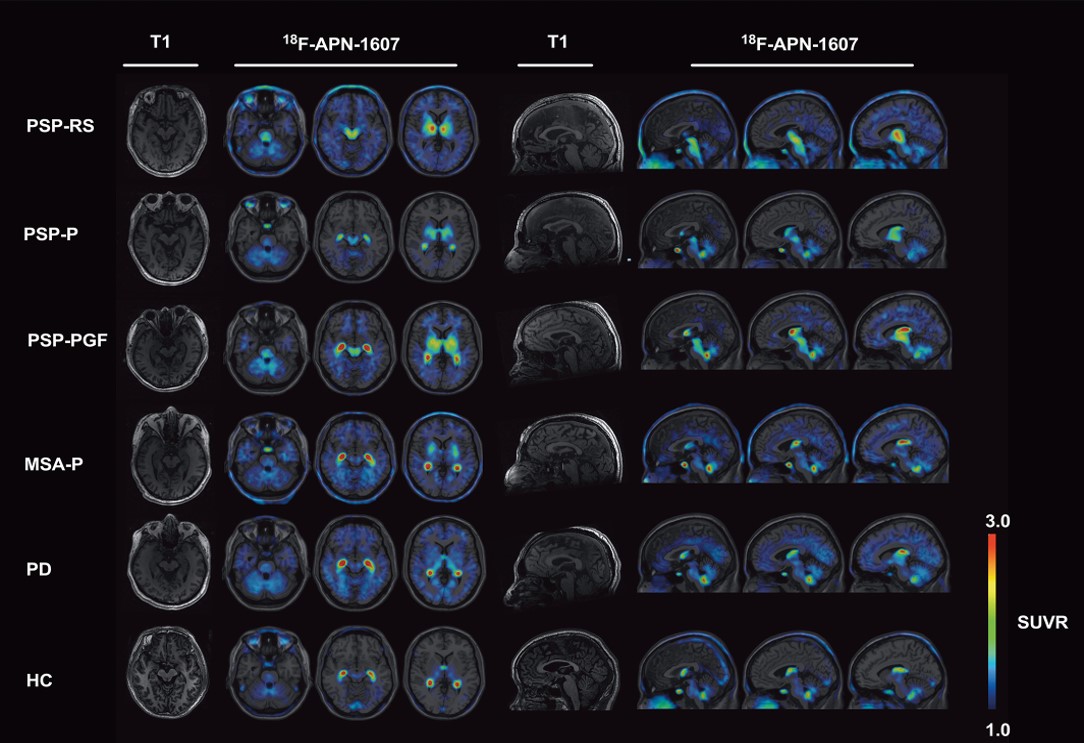

The news flash is that [18F]-APN-1607, has leapt ahead of [18F]-PI-2620, at least for now.  (Not that we shouldn’t have multiple tau PET ligands for PSP with slightly different properties for different clinical situations – that would be great!)  The paper of Li et al included 20 patients with PSP (a lot for an early-phase PET study), of whom 16 had probable PSP-Richardson syndrome, 2 had PSP-parkinsonism, 1 had PSP-progressive gait freezing and 1 had “suggestive of” PSP.  Their average PSP Rating Scale score was 31.6, which is toward the milder end of the range typical of PSP drug trials and milder than the patients in the l[18F]-PI-2620 trial.  There were also 7 with MSA-parkinsonism, 10 with Parkinson’s disease (both of which are alpha-synucleinopathies, not tauopathies) and 13 healthy controls.  The results were corrected for any effects of age, sex, or disease duration and for multiple comparisons.

The study found that [18F]-APN-1607 PET shows major differences between PSP and healthy controls in 12 brain regions known from autopsy studies to be affected most in PSP. The same could be said for the comparisons of PSP with Parkinson’s or MSA-P, although when only the putamen (part of the basal ganglia) was considered, 4 of the 7 patients with MSA-P had as much binding as those with PSP.  So the authors combined the measurements from the substantia nigra (part of the midbrain, which is part of the brainstem) with those of the putamen, achieving much better separation.  Still it was far from perfect: The standard measure of diagnostic accuracy at an individual patient level, as opposed to merely comparing two groups’ average measurements, is the area under the receiver operating curve (AUC).  That statistic, where perfect is 1.0 and useless is 0.5, takes into account both sensitivity and specificity.  The AUC based on [18F]-PI-2620 uptake in putamen and midbrain for PSP vs the synucleinopathies was 0.811 and for PSP vs. controls, 0.909.  Good but not great.

When they homed in on the subthalamic nucleus, a tiny area that may be where PSP starts in the brain, the AUC was an excellent 0.935 (0.975 for MSA-P and 0.908 for PD).  But that nucleus is so small relative to the spatial resolution of PET that it could be a problem to train large numbers of radiologists and technicians to measure it in the real world using real-world hardware and software.

In the figure above, the first and fifth columns are the MRI images used as templates on which the PET images (the colored areas in the other columns) are superimposed. The group of images on the left are axial images through the planes of (from left to right) the pons, midbrain and putamen. On the right are sagittal images through planes a bit left of midline, midline and a bit right of midline. Each row is one patient with the condition listed at the far left. (HC means healthy control.) Note that all three subtypes of PSP show strong uptake of the tracer in the putamen and midbrain and none of the other patients shows this combination. The brain area with the greatest difference between PSP and non-PSP, the subthalamic nucleus, is too small to appear to the naked eye as a clear and separate dot in these images.